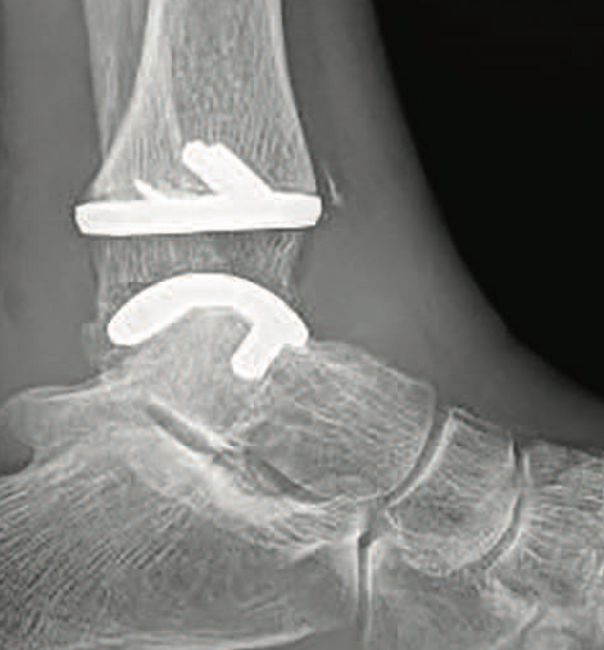

Test Your Knowledge: More on TAR Basics